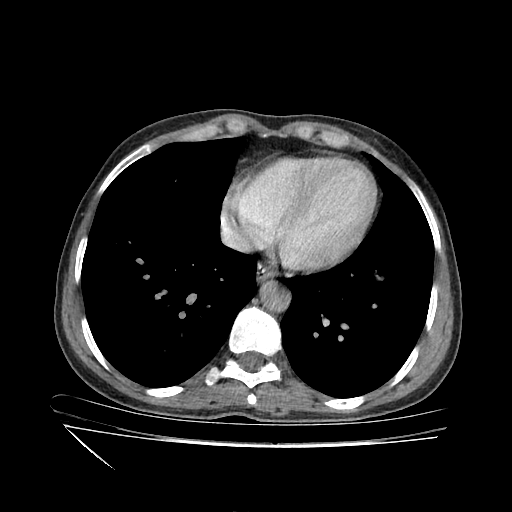

Slice 70 Targeting Evaluation

Slice: Slice_70

Conversion: NATIVE β†’ VENOUS

Image Grid

4Γ—3 grid: Rows show different image types (Original NATIVE, Reconstructed NATIVE, Original VENOUS, Generated VENOUS), Columns show windowing techniques (No Window, Lung Window, Mediastinum Window)

Original VENOUS CT scan

No window - Raw intensity values